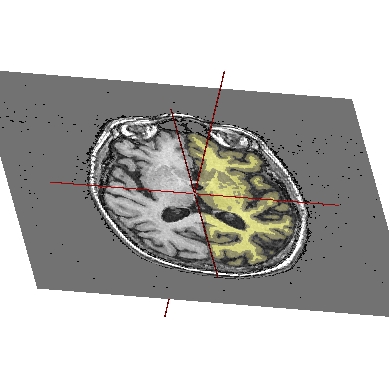

STEP 1: Load the images to merge. Here, we will fusion an anatomy and the brain mask obtained from BrainVISA anatomical pipeline.

STEP 2: Select the two volumes in objects list with Ctrl + left button.

STEP 3: Then click on fusion button

.STEP 4: A new window pop up to select objects order and fusion type (fusion types offered differs according to selected objects, this will be detailled later, in advanced part of the manual).

STEP 5: Click on Ok to create the new Fusion2D object.

STEP 6: Put the Fusion2D object in a window.

STEP 7: If the Fusion2D object is all in black, you must change fusion mode. So right click on Fusion2D object to get its menu. Choose Fusion => Control 2D fusion. This window opens:

Fusion control¶

STEP 8: You can change the mapping mode. The default is Linear: it does a linear combination of the two volumes. The Geometric mode does RGB channels multiplication. For linear fusions, you can set objects transparency with the cursor Mixing rate.

STEP 9: By default, the 2 volumes will have the same palette. To change at least one, do Right clik menu on a volume => Color => Palette.

Example of a linear fusion between two 3D volumes¶